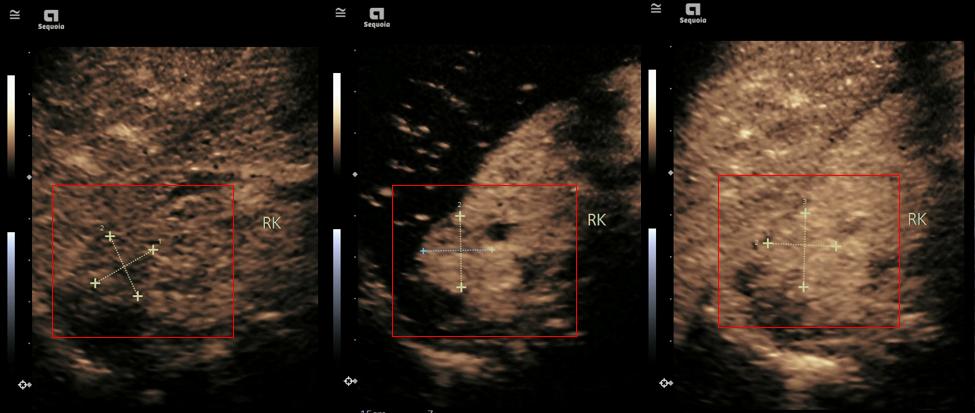

肾脏肿瘤造影图像显示